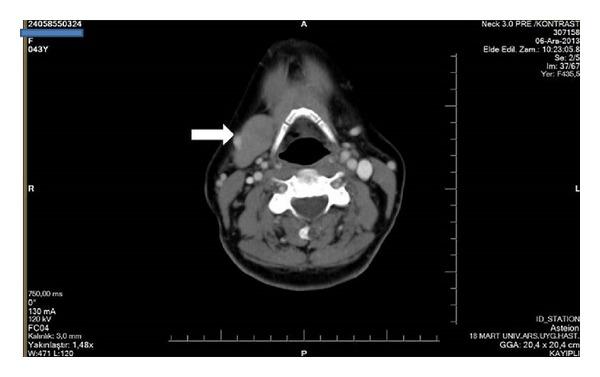

Background. Congenital absence of the submandibular gland (SMG) is a rare condition. Although complaints such as dry mouth, dental problems, or difficulty in swallowing may be seen, the subjects may also be asymptomatic. The absence of the SMG may be associated with hypertrophy of the contralateral SMG. Case Report. We report the case of a 44-year-old woman with incidentally detected left SMG aplasia, with contralateral SMG hypertrophy mimicking a mass, and the case of a 46-year-old woman with incidentally detected bilateral SMG aplasia, demonstrated by computerized tomography (CT) and magnetic resonance imaging (MRI). Conclusion. It is important for the clinician to know that this very rare abnormality may exist. When such a case is encountered, symptoms and findings should be reevaluated and, if necessary, conservative therapy should be initiated. The possibility of observing additional deformities should be kept in mind and an evaluation should be done for other cases in the family.

背景。先天性下颌下腺缺如(SMG)是一种罕见的病症。尽管可能会出现口干、牙齿问题或吞咽困难等症状,但患者也可能没有症状。SMG缺如可能与对侧SMG肥大有关。病例报告。我们报告了一例44岁女性,偶然发现左侧SMG发育不全,对侧SMG肥大类似肿块;以及一例46岁女性,偶然发现双侧SMG发育不全,通过计算机断层扫描(CT)和磁共振成像(MRI)得以证实。结论。临床医生了解这种非常罕见的异常情况可能存在很重要。遇到此类病例时,应重新评估症状和检查结果,必要时应开始保守治疗。应牢记观察到其他畸形的可能性,并对家族中的其他病例进行评估。